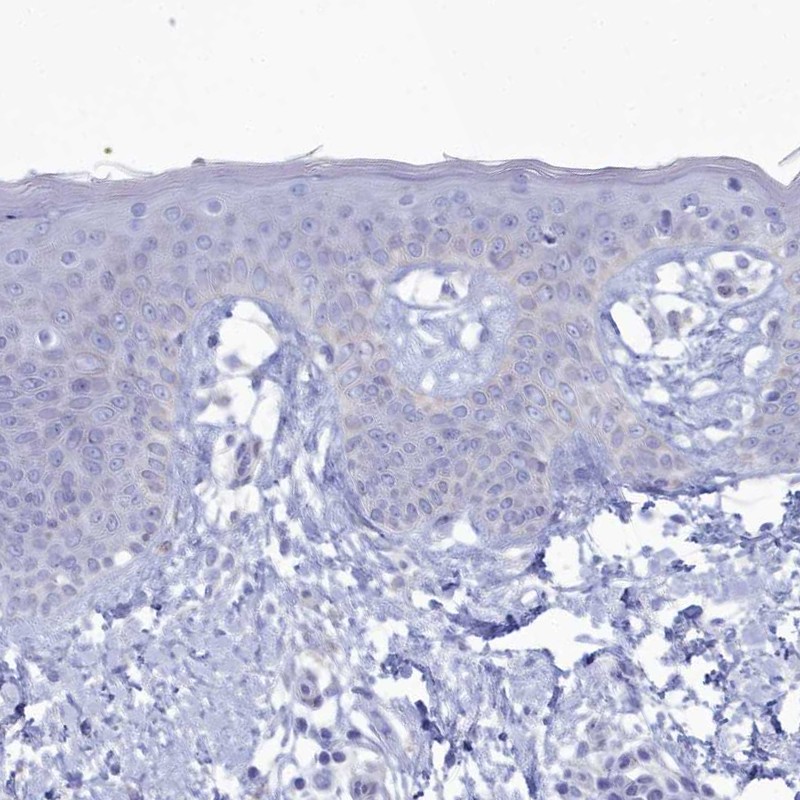

Immunohistochemistry analysis in human cerebral cortex and skin tissues using Anti-PPP1R14A antibody. Corresponding PPP1R14A RNA-seq data are presented for the same tissues.